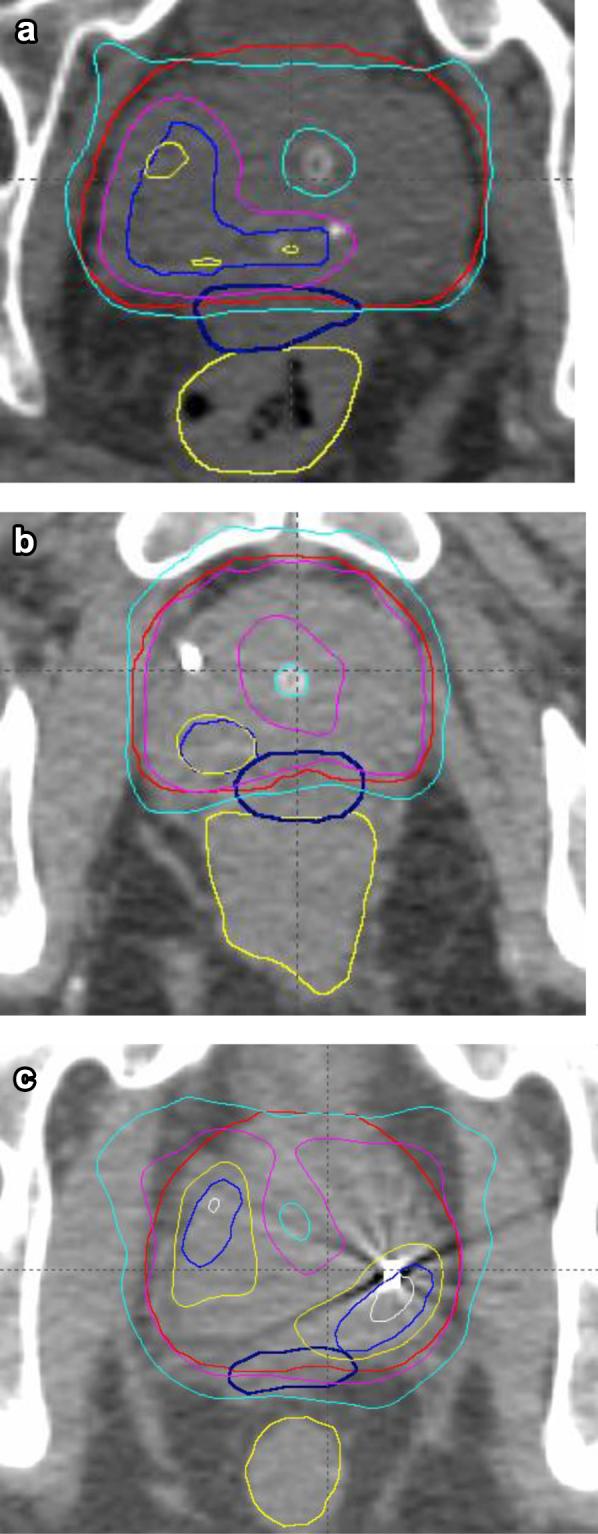

To demonstrate feasibility and toxicity of linear accelerator-based stereotactic radiation therapy boost (SBRT) for prostate cancer, mimicking a high-dose-rate brachytherapy boost.

METHODS AND MATERIALS

A phase 1 sequential dose escalation study of SBRT compared 20 Gy, 22 Gy, and 24 Gy to the prostate and 25 Gy, 27.5 Gy, and 30 Gy to the gross tumor volume in 2 fractions, combined with 46 Gy in 23 fractions of external beam radiation. Feasibility of dose escalation (volume receiving 125% and 150% of the dose) while meeting organ-at-risk dose constraints, grade 2 acute and late gastrointestinal and genitourinary toxicity, and freedom from biochemical failure were secondary endpoints.

证明基于直线加速器的立体定向放射治疗增敏(SBRT)用于前列腺癌的可行性和毒性,模拟高剂量率近距离放射治疗增敏。

方法和材料

一项SBRT的1期序贯剂量递增研究比较了20Gy、22Gy和24Gy给予前列腺,以及25Gy、27.5Gy和30Gy给予大体肿瘤体积,分2次给予,联合外照射46Gy分23次给予。在满足危及器官剂量限制的同时剂量递增(接受125%和150%剂量的体积)的可行性、2级急性和晚期胃肠道及泌尿生殖系统毒性以及无生化失败是次要终点。